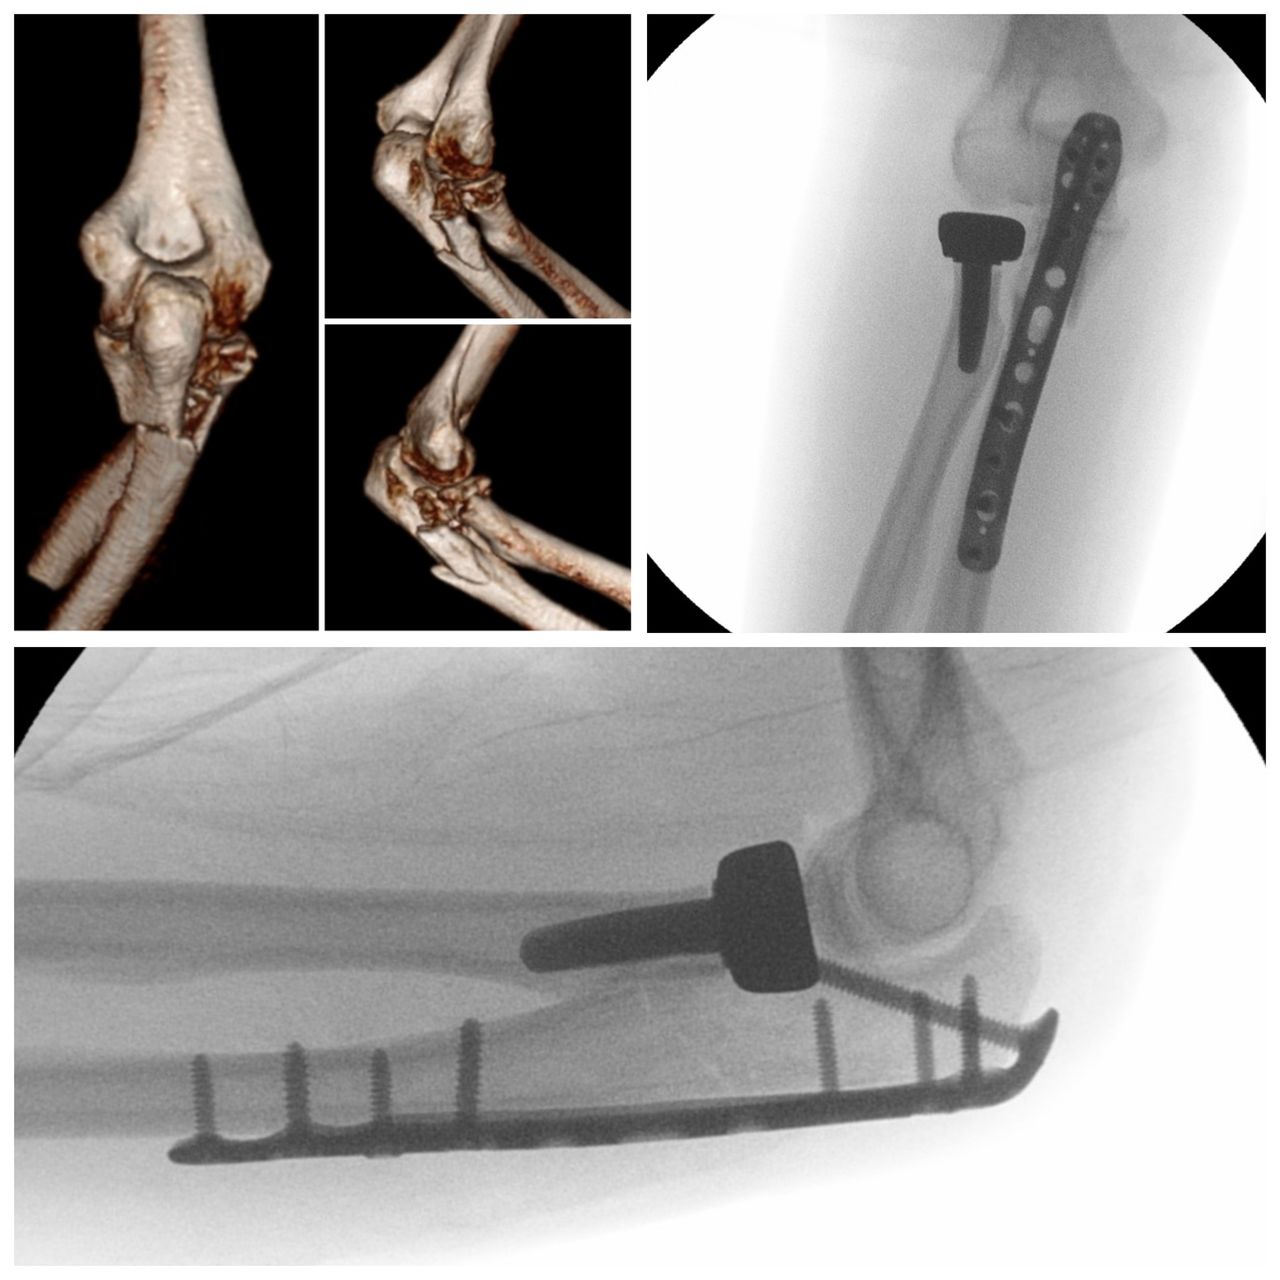

Se especializa en Síndrome del Manguito Rotador, Artroscopía de Hombro, Luxación de Hombro, Epicondilitis Lateral (Codo de Tenista), Fractura de Clavícula, Disyunción Acromioclavicular, Fracturas de Codo.

Conferencista. Tríada Terrible del Codo. II Jornadas de Traumatología. Hospital Universitario de Caracas (HUC). Caracas, Venezuela. 2015